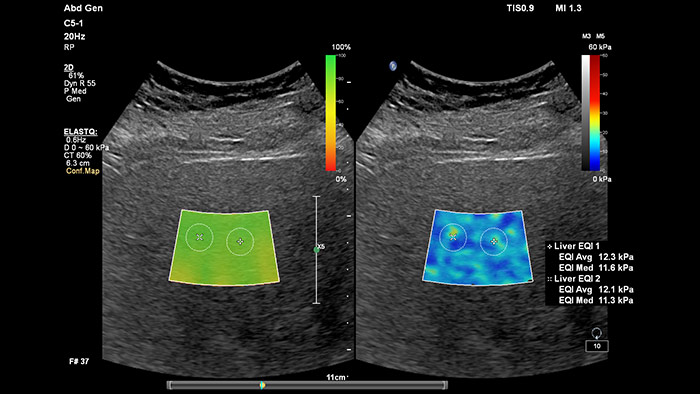

Elastografía por onda transversal de imágenes con ElastQ

La elastografía por ultrasonidos de onda transversal ofrece un método no invasivo, reproducible y fácil de poner en práctica para evaluar la rigidez tisular. Los estudios realizados apuntan a que, en lugar de un costoso y doloroso procedimiento de biopsia, una sencilla exploración por ultrasonidos con elastografía de onda transversal podría convertirse en el procedimiento habitual para evaluar el estado de las enfermedades hepáticas.  La elastografía por onda transversal de alto rendimiento de las imágenes con ElastQ incluye la evaluación cuantitativa de la rigidez tisular, codificada con colores, en extensas regiones de interés (ROI) en tiempo real.  Las imágenes con ElastQ también ofrecen la posibilidad de efectuar mediciones retrospectivas en imágenes almacenadas; además, una exclusiva pantalla con un mapa de confianza emplea el análisis inteligente para ofrecer la garantía adicional de que las mediciones del usuario se han obtenido en zonas tisulares con una propagación adecuada de ondas transversales.